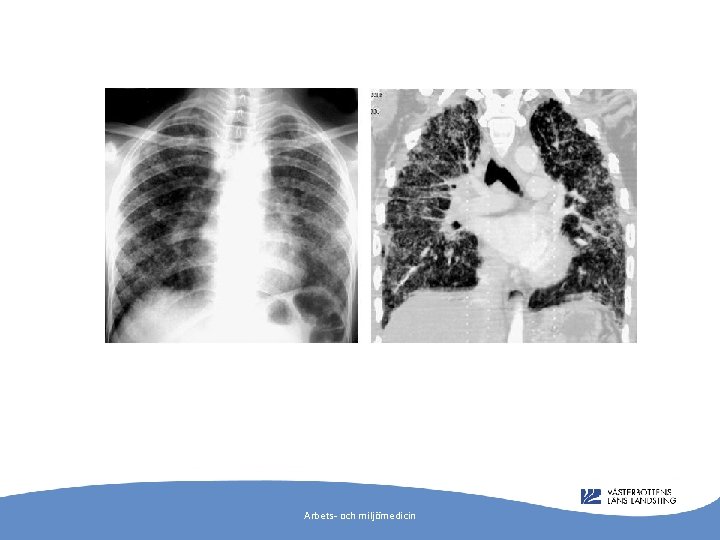

”A 17 -year-old man presented to hospital with dry cough and pleuritic chest pain. For approximately 2 years he had worked in a textile factory as a denim sandblaster using silica-containing sand to abrade denim material. ” Arbets- och miljömedicin

Silikos - stendammlunga Cimrin et al: Sandblasting jeans kills young people. ERJ 28(4); 885 -6. 2006. Akgun et al: N Z Med J. 2008 May 9; 121(1273): 69 -71. Arbets- och miljömedicin